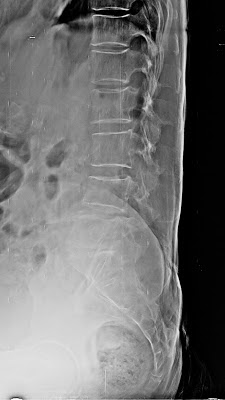

bronchi. There is lot of overlap of bronchopulmpnary segments on a PA view of

chest but they project separately on a lateral view. Their approximate location

as seen on frontal and lateral radiographs is illustrated

| Right lung on lateral projection |

Left lung on lateral projection